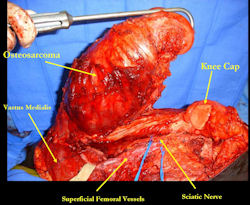

Examples of radical limb sparing surgeries for osteosarcomas in various anatomic locations (distal femur, proximal tibia, proximal humerus, scapula)

In each case, the tumor and bone from which it arose were resected. This required meticulous dissection, mobilization and preservation of adjacent pertinent neurovascular structures. In each case presented here, the defect was reconstructed with a special modular segmental tumor prosthesis. This also replaces the adjacent joint in many instances.

Limb-sparing surgery for osteosarcoma of distal femur – Intraoperative photos